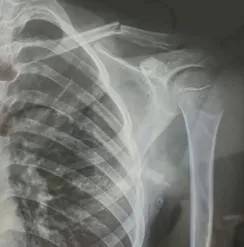

10月23日,内蒙古赤峰市宁城县苏木皋小学一学生被老师打伤致锁骨骨折。10月31日,家长贾女士给生活报记者打来电话称,事件已经过去一周时间了,但是校方还没有到医院给孩子道歉,且涉事教师还在上班。

图片由报料者提供